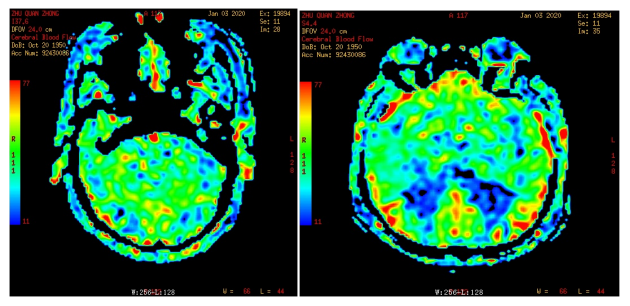

3D ASL (动脉自旋标记灌注成像) 正常图像